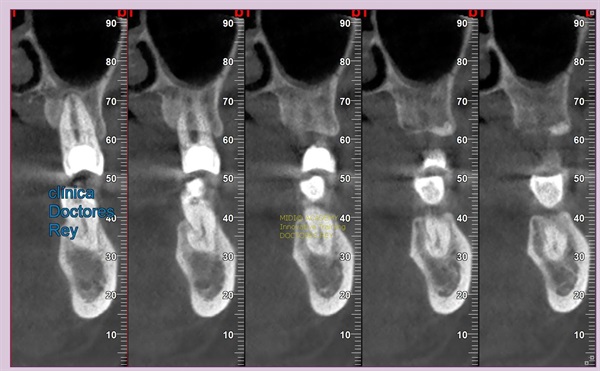

2-Implantes monobloque, en maxilar inferior. MIDI® TECHNIQUE® -US.

4x11,5. colocados con técnica ultarasónica MIDI®, hueso de calidad baja.

1- Implante de 9 mm de diámetro en maxilar superior post extracción + PRF. MIDI® TECHNIQUE®, no drill.

IMPLANTE EN MAXILAR SUPERIOR post extracción de diametro amplio 9 mm.

1- Implante de 9 mm de diámetro en maxilar superior post extracción + PRF. MIDI ®TECHNIQUE®, no drill.